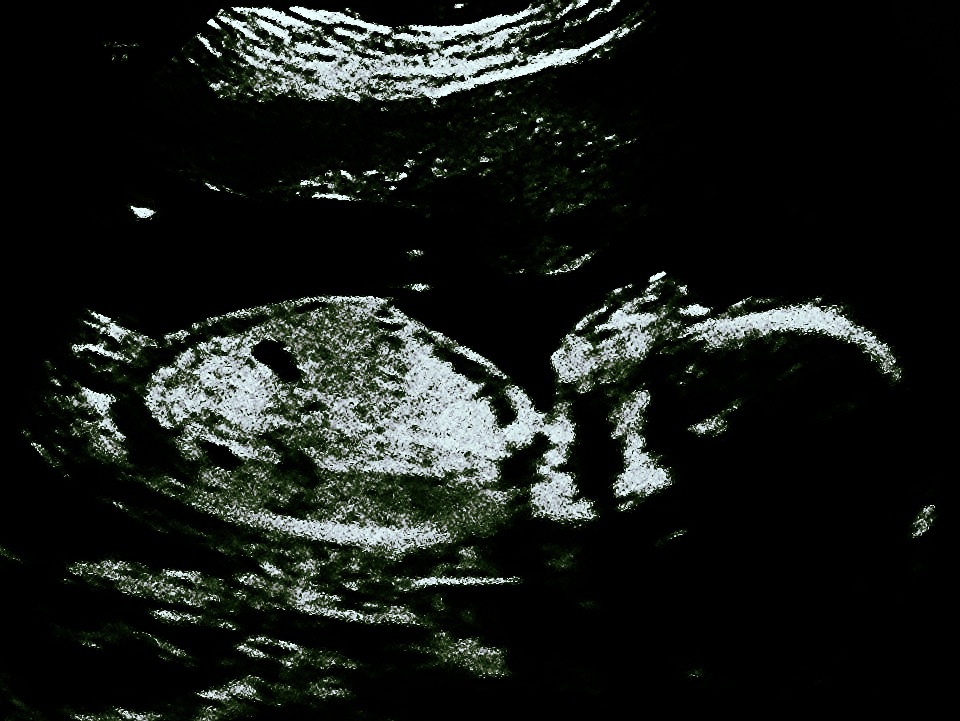

Try and zoom in xx

At 19 weeks you really need a potty shot!

I think girl!

Quote: Originally Posted by myrainbowgirl I think girl! Hi :) thanks! If u don't mind me asking what makes you think girl? Xx